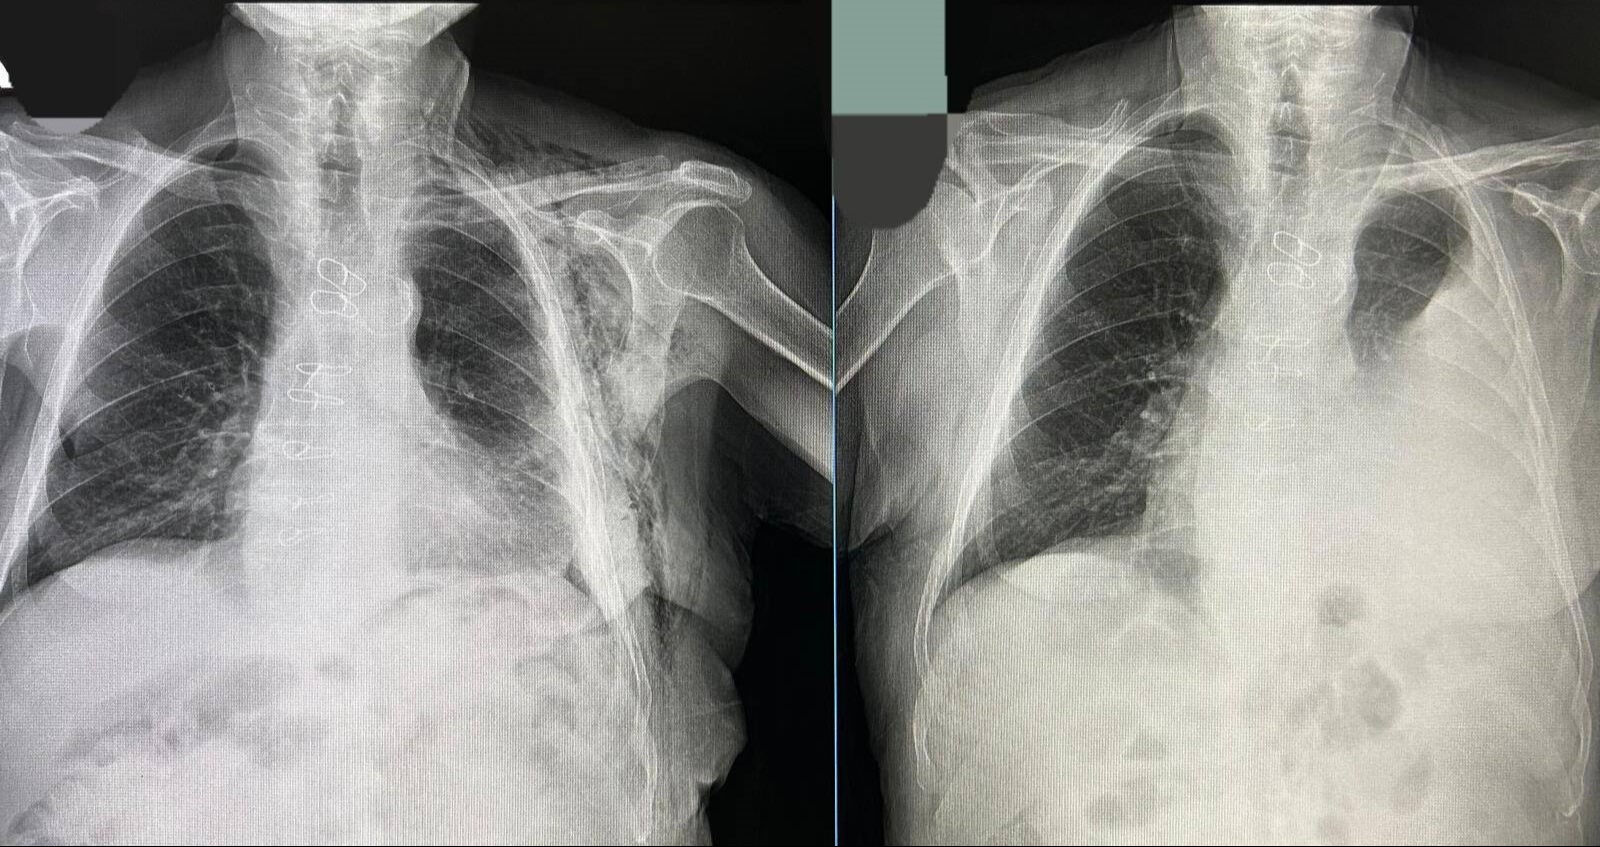

Bypass ameliyatı sonrası Göğüs Cerrahisi Polikliniğine kontrole giden hastanın göğüs boşluğunda sıvı biriktiği tespit edildi.

Tüp torakostomiye dirençli efüzyon nedeniyle değerlendirmeye alınan hastaya Göğüs Cerrahisi Uzmanı Op. Dr. Halil Kolcu tarafından kapalı yöntemle akciğeri serbestleme ameliyatı yapıldı.

Başarılı geçen operasyonla hastanın akciğerinin yeniden genişlemesi sağlanırken, sıvı birikiminin önüne geçildi. Hastanın ameliyat sonrası sürecinin sorunsuz ilerlediği ve altıncı günde taburcu edildiği öğrenildi.